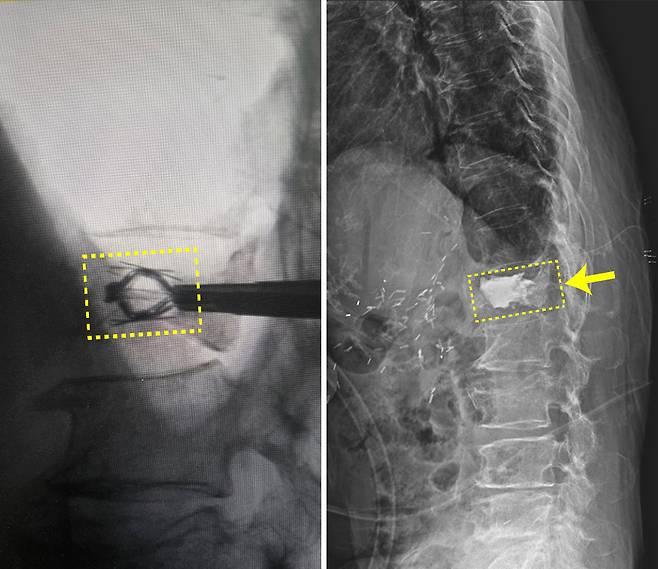

김중호 신경외과 과장은 “임플란트를 이용한 경피적 척추 압박 골절 보강술은 척추체에 상하 축 확장형의 티타늄 임플란트를 삽입해 압박 골절된 척추체를 들어 올린 후 골시멘트를 주입하는 방식”이라며 “임플란트의 삽입 위치와 팽창을 집도의가 제어할 수 있어 무너진 척추체를 보다 정확한 높이로 복원하는데 유리하다”고 말했다.

심한 척추 압박 골절에는 주로 풍선 척추성형술을 시행해 왔다. 골절된 척추체 부위에 특수 풍선이 부착된 카테터를 삽입해 풍선을 부풀려 척추체를 원래 상태로 회복시킨 후, 그 공간에 골 시멘트를 주입하는 방식이다. 다만 풍선을 부풀리는 과정에서 저항이 약한 쪽으로 더 부풀려지는 등의 한계도 있다.